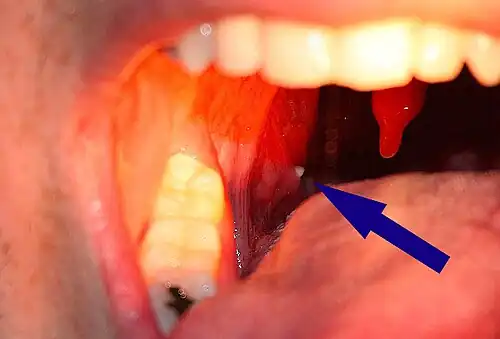

Tonsil stones, also known as tonsilloliths, are mineralizations of debris within the crevices of the tonsils.[1][3] When not mineralized, the presence of debris is known as chronic caseous tonsillitis (CCT).[1] Symptoms may include bad breath,[1] foreign body sensation, sore throat, pain or discomfort with swallowing, and cough.[4] Generally there is no pain, though there may be the feeling of something present.[1] The presence of tonsil stones may be otherwise undetectable; however, some people have reported seeing white material in the rear of their throat.

A tonsillolith protrudes from the tonsil -

Large tonsillolith half exposed on tonsil

Enlarged tonsil stones

Much rarer than the typical tonsil stones are giant tonsilloliths. Giant tonsilloliths may often be mistaken for other oral maladies, including peritonsillar abscess, and tumors of the tonsil.[17] On average, tonsil stones should appear within a similar range of the image shown here; however, individuals with extenuating cases have been reported. In these instances, extensive care such as extraction by a licensed medical professional may be needed.